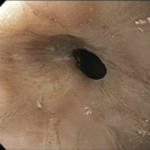

Electrohydraulic Lithotripsy for Biliary and Pancreatic Stones

Electrohydraulic lithotripsy (EHL) has emerged as a vital adjunct to endoscopic retrograde cholangiopancreatography (ERCP), providing an effective means of fragmenting large, impacted, or otherwise difficult-to-extract stones within the pancreatic and […]